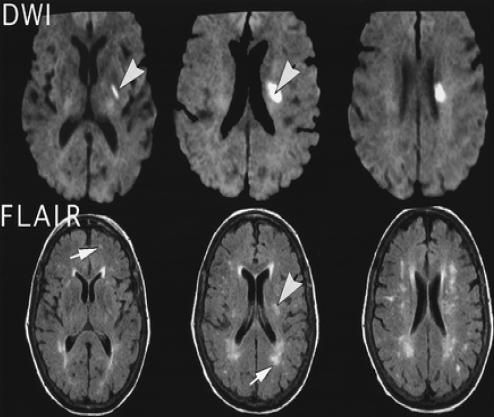

Nhồi máu não ổ khuyết cạnh não thất bên phải

Nhồi máu não chiếm tỷ lệ khoảng 80% đột quỵ não, 20% còn lại là chảy máu não, chảy máu dưới màng nhện. Bài viết này sẽ nói rõ hơn về hội chứng Nhồi máu não ổ khuyết cạnh não thất bên phải. Mời các bạn tham khảo!

Trên đây là một số thông tin và hình ảnh về hội chứng Nhồi máu não ổ khuyết cạnh não thất bên phải, hy vọng sẽ giúp các bạn có hướng điều trị bệnh kịp thời và hiệu quả!